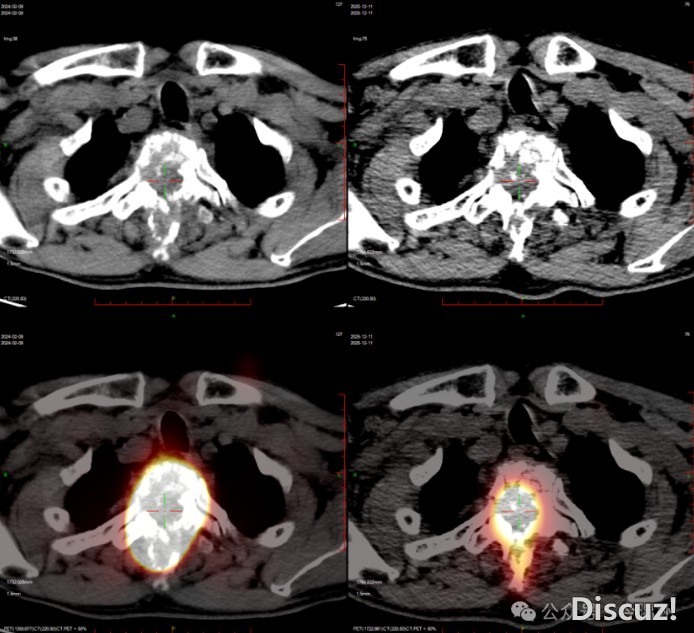

胸椎转移瘤伴脊髓压迫治疗后,病灶缩小

治疗过程比林伯想象的简单多了:就像喝普通盐水似的,一口喝下“药水”,然后在核素防护病房里隔离一段时间,等辐射衰减达标就能出院。随着治疗推进,奇迹慢慢发生:林伯感觉腿上有了知觉,原本麻木的双腿渐渐能轻微活动,再后来,在侄子的搀扶下能坐起来,最后竟能拄着拐杖慢慢走路了!复查显示,他胸椎上的转移灶明显缩小,脊髓压迫减轻,神经功能在逐步恢复。